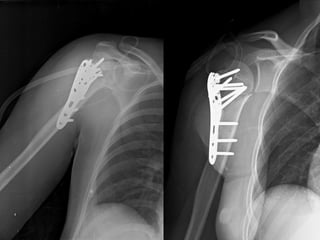

CXR

Film right arm AP, transcapular Y view

CT

Diagnosis

• Closed fracture right proximal humerus (4 parts)

Imaging • Radiographs • completetrauma series – true AP – scapular Y – axillary • CT scan – indications • preoperative planning • humeral head or greater tuberosity position uncertain • intra-articular comminution • MRI – indications • rarely indicated • useful to identify associated rotator cuff injury